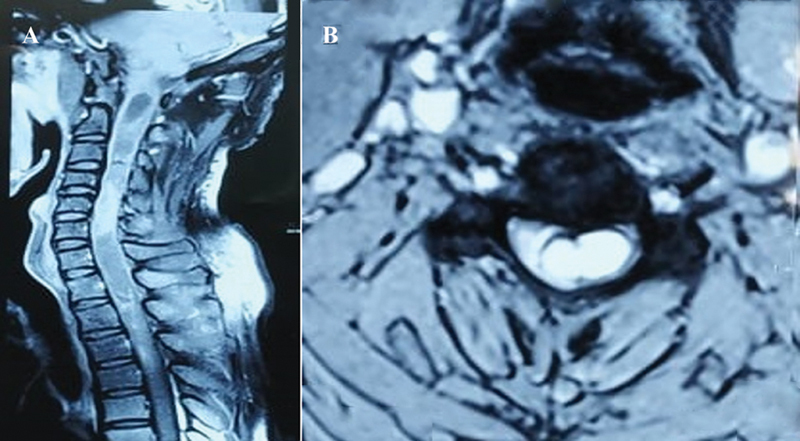

Neurenteric cysts, also known as endodermal or enterogenous cysts, are uncommon benign congenital lesions of the central nervous system (CNS) characterized by an epithelial lining of endodermal origin. These cysts predominantly affect the spinal canal and cord. Intramedullary neurenteric cysts are exceptionally rare, with fewer than 100 reported isolated cases. Their distinct characteristics, clinical presentation, and challenges in diagnosis and treatment necessitate a detailed case analysis and review. We present the case of a 33-year-old male patient with an intriguing case of an isolated intramedullary cystic lesion in the cervicodorsal spinal cord, extending from the cervicobulbar junction to the D4 vertebra level. The patient's clinical presentation included a 6-month history of progressive weakness in the left upper limb, accompanied by pain and numbness. Neurological examination revealed muscle atrophy, reduced strength, spastic paraparesis, and sensory deficits. Radiological findings demonstrated an expansile cystic lesion with marked signal heterogeneity, intense enhancement, and the presence of a "cap sign" indicative of subacute hemorrhage. Diagnosis of spinal intramedullary neurenteric cysts is reliant on histopathology. Surgical removal remains the recommended treatment, as a conservative approach can lead to irreversible neurological deficits. However, complete resection may be challenging due to potential adhesions to surrounding structures. In such cases, a more conservative approach, avoiding cyst spillage into the subarachnoid space, is preferred. Vigilant radiological follow-up is crucial to monitor for potential cyst recurrence. These rare cases highlight the need for further scientific literature and improved diagnostic and therapeutic strategies.